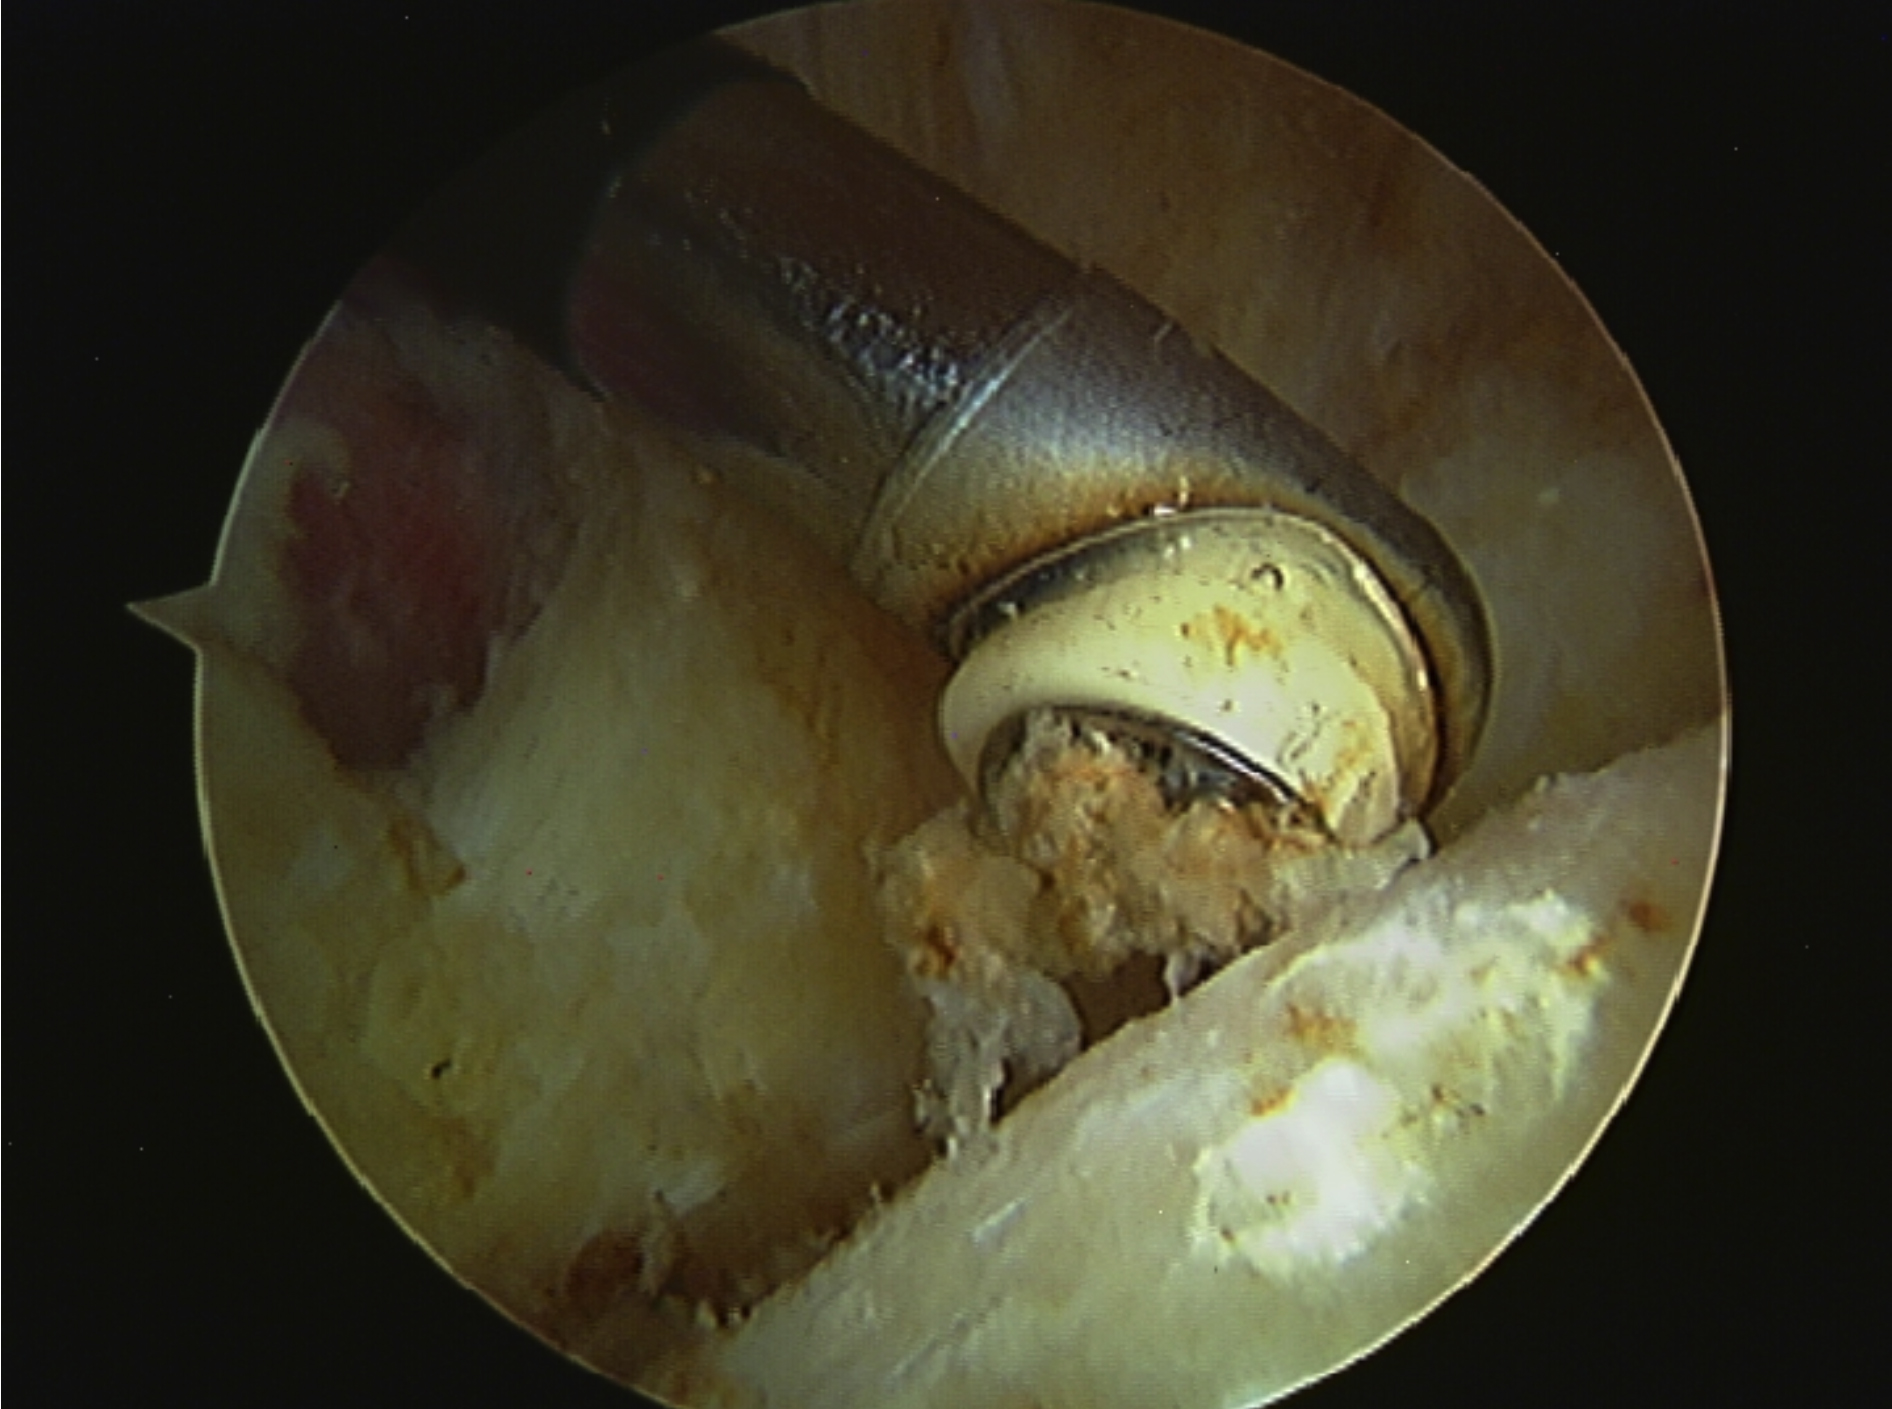

Fig. 1: 26-year old professional footballer with significant chondral damage secondary to cam FAI.